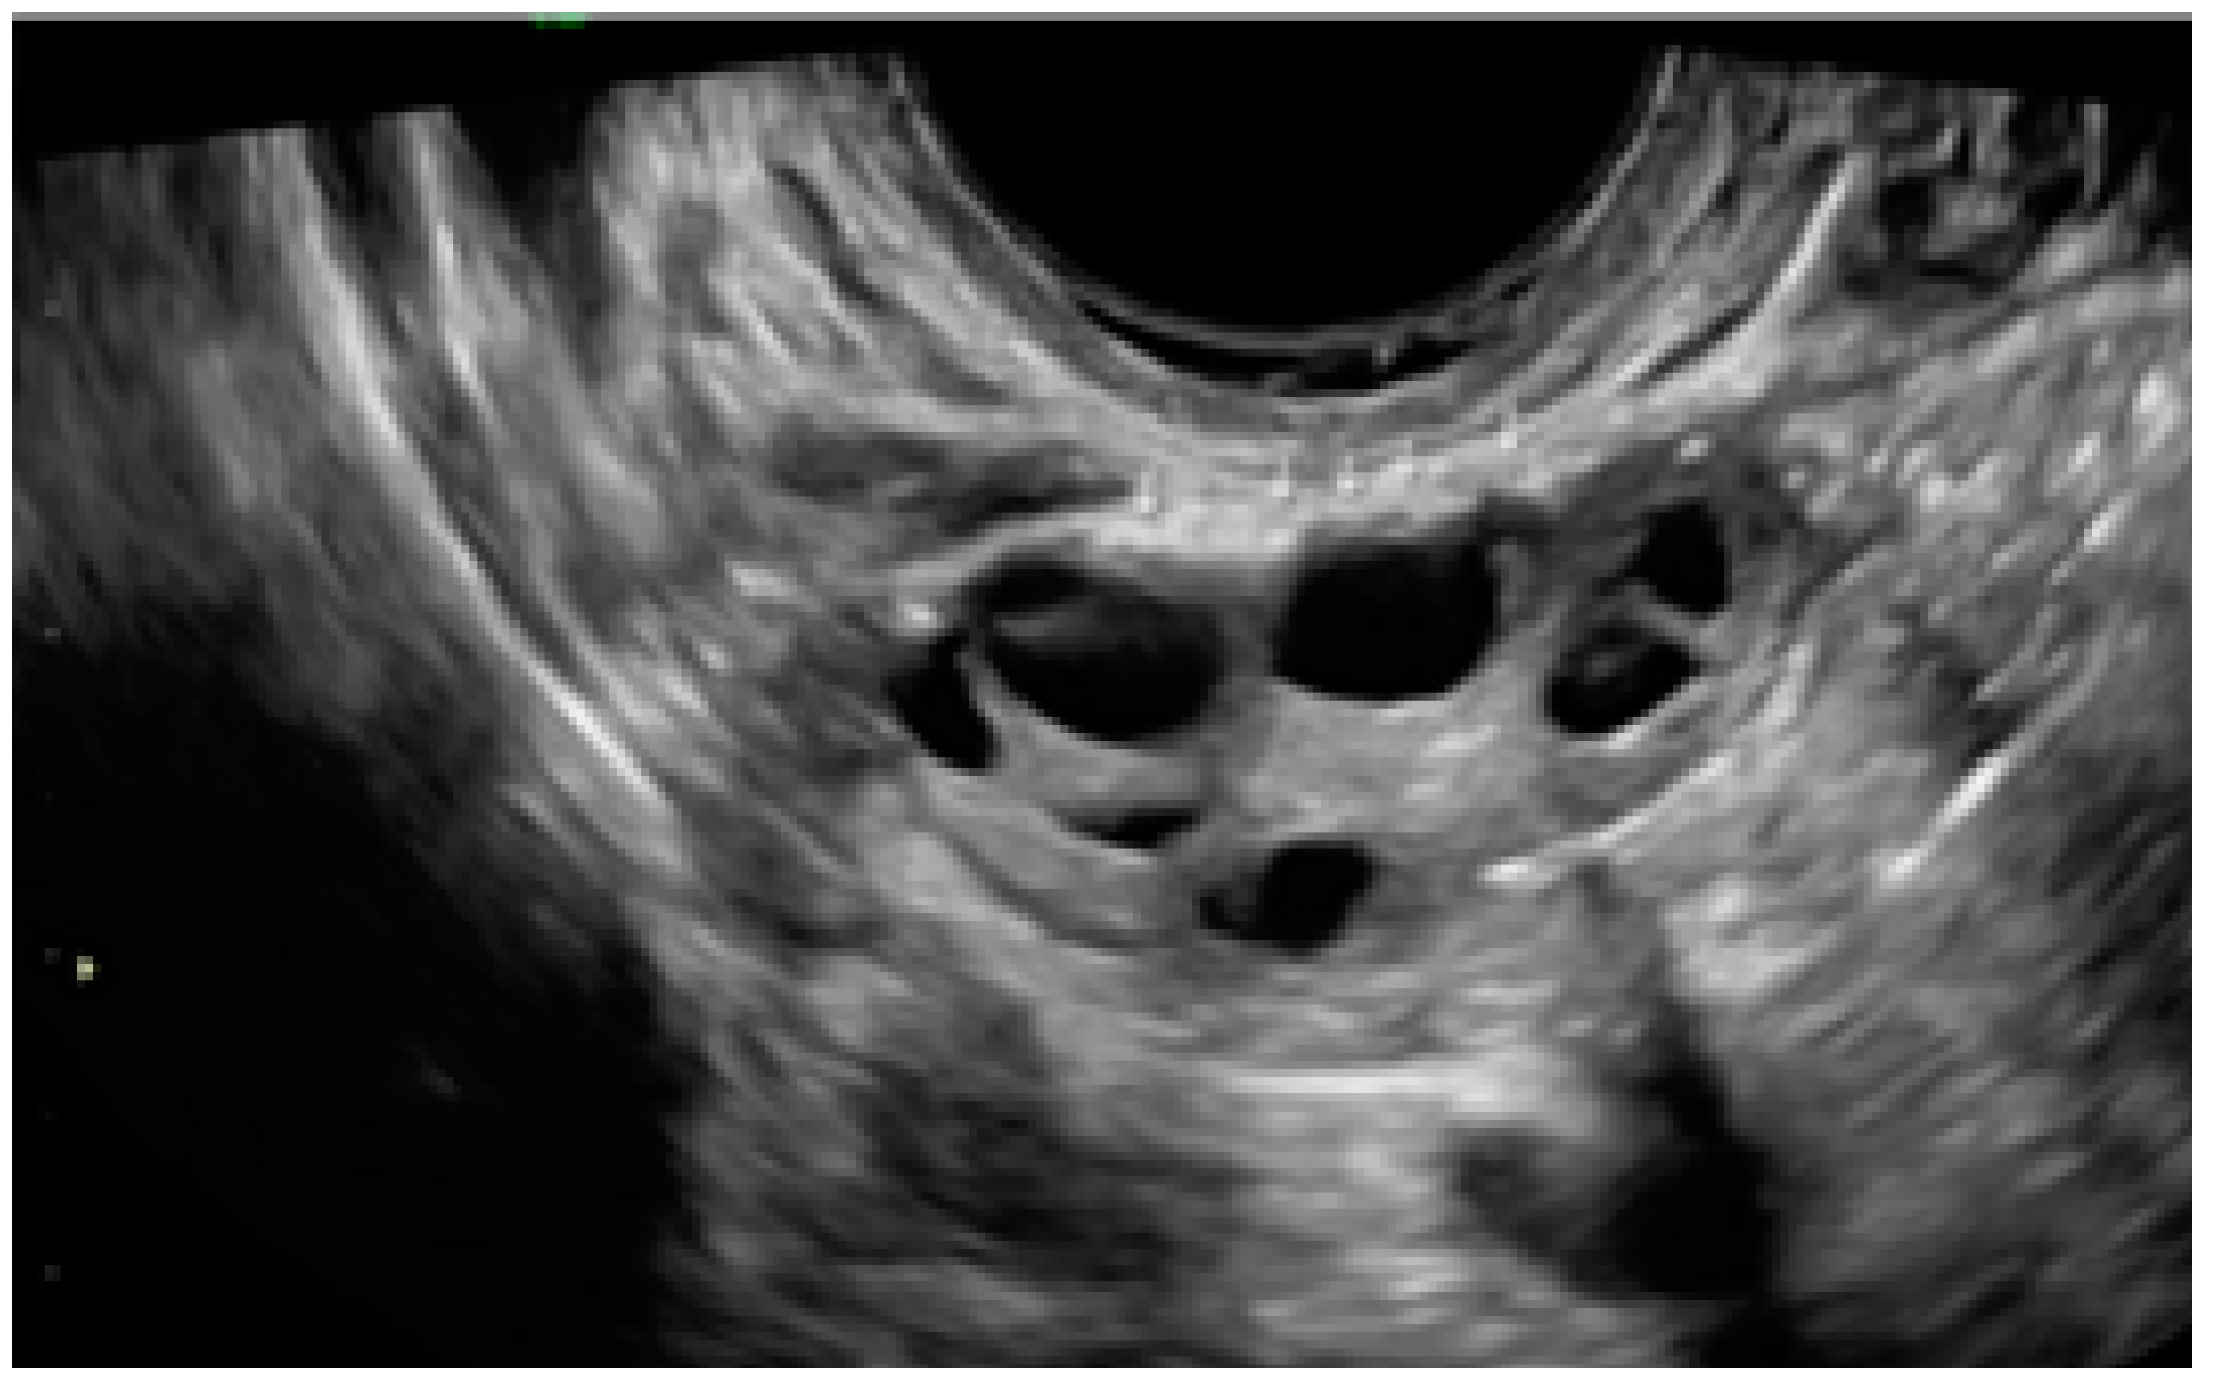

3.2. Cystic Multiple Separate Lesions

3.3. Cystic Lesions Arranged in a Cluster